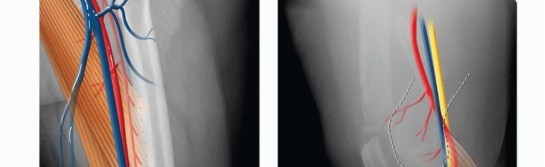

### FIG 4 • A,B. Coronal and sagittal CT angiography images showing intact femoral artery in a severely comminuted distal femur fracture (red arrows). Dedicated knee films should always be obtained in the assessment of distal femur fractures. Additionally, the entire femur, to include the hip and knee, should be imaged to look for possible extension and associated injuries and to allow for preoperative planning ( FIG 5). In cases of severe comminution, radiographs of the contralateral knee can aid in preoperative planning as well. A dedicated CT scan is an important adjunct to the preoperative planning when there is articular involvement ( FIG 6). Generally, extra-articular distal femur fractures do not require a CT scan. However, it has been shown that coronal fractures may be missed on plain films, and thus there is a low threshold for obtaining a CT scan for fractures of the distal femur. 11 If the fracture pattern warrants a temporary bridging external fixator, it is best to obtain the CT scan after placement of such a fixator for better definition. Coronal and sagittal reconstructions should be requested. Three-dimensional images can be created from most CT scans. This can also aid in the preoperative planning ( FIG 7A,B). Subtle sagittal plane rotational malalignment between condyles can be assessed ( FIG 7C). If associated soft tissue injury is suspected, such as ligamentous tears or tendon ruptures, then magnetic resonance imaging (MRI) may be indicated. Routine use of MRI, however, is not needed. ## DIFFERENTIAL DIAGNOSIS Proximal tibia fracture Femoral shaft fracture Septic knee Patella fracture Anterior cruciate ligament rupture Knee dislocation ## NONOPERATIVE MANAGEMENT There are few relative indications for nonoperative management of distal femur fractures: Poor overall medical condition Patient has severe comorbidities and is too sick for surgery. Patient has extremely poor bone stock. Spinal cord injury (paraplegia or quadriplegia) Some special situations may warrant nonoperative care on case-by-case basis. Nondisplaced or minimally displaced fracture Select gunshot wounds with incomplete fractures Extra-articular and stable Unreconstructable Lack of experience by the available surgeon or lack of equipment or appropriate facility to adequately treat the injury. Transfer is indicated in these situations; otherwise, nonoperative treatment may be the only option. There are several methods for nonoperative treatment. Skeletal traction Cast bracing Knee immobilizer Long-leg cast There are acceptable limits for nonoperative management: Seven degrees of varus or valgus Ten degrees of anterior or posterior angulation. A flexion deformity is less well tolerated than an extension deformity. Up to 1 to 1.5 cm of shortening Two to 3 mm of step-off at the joint surface 469

* FIG 2 • Mechanical and anatomic axes of the lower extremity; the 9 degrees of valgus at the knee is noted. The neurovascular structures about the knee are at risk when an injury of the distal femur occurs. At the canal of Hunter, roughly 10 cm proximal to the knee on the medial side, the superficial femoral artery enters the popliteal fossa (see FIG 3C). Posterior to the knee, both the popliteal artery and the tibial nerve are at risk at the fracture site ( FIG 3D). ## PATHOGENESIS As mentioned, there is a bimodal distribution in terms of age in the epidemiology of distal femur fractures. This relates to the mechanism of injury. High-energy and low-energy injuries occur. High-energy injuries usually are from motor vehicle accidents and occur in the young patient. There is a direct impact onto the flexed knee, such as from the dashboard. These patients often have associated injuries such as a hip fracture or dislocation or vascular or nerve injury. These high-energy injuries generally result in comminuted fractures, mostly of the metaphyseal region. The comminution can be articular as well. Low-energy injuries usually occur in the elderly patient who falls from a standing height. The axial loading is accompanied by either varus or valgus with or without rotation. The osteoporotic bone in these individuals leads to fracture. The fracture pattern can vary from the most simple extra-articular type to the most complex intraarticular injury. Owing to the gastrocnemius complex, an apex posterior deformity of the condyles occurs as the fragments are flexed because of the muscle attachment. ## NATURAL HISTORY Fractures of the distal femur that have intra-articular displacement can lead to severe posttraumatic arthritis if left untreated. Operative treatment has led to a 32% decrease in poor outcomes. 19 ## PATIENT HISTORY AND PHYSICAL FINDINGS Direct physical examination of the knee with a distal femur fracture is limited primarily because of pain and the obvious nature of the injury. The patient presents with a swollen and tender knee after either a fall or some high-energy trauma (motor vehicle or motorcycle accident). A large hemarthrosis is present. Any attempts at range of motion result in severe pain, and significant crepitus is usually noted with palpation. If there is concern for an open knee joint, the joint can be injected after a sterile preparation to see whether the knee joint communicates with any wound. The physical examination is directed primarily at ascertaining the neurovascular status of the lower limb and determining whether any associated injuries exist, especially the hip (see Exam Table for Pelvis and Lower Extremity Trauma, pages 1 and 2). If there are any small wounds or tenting of the skin anteriorly, the fracture should be considered as being open. It is important to check for pulses. If diminished or absent, pulses should be assessed with Doppler. The ankle-brachial indices should be obtained if there is a concern for arterial injury. Any side-to-side difference or value less than 0.9 warrants an arteriogram. Computed tomography (CT) arteriogram has been used with increasing frequency as well in cases where there is concern ( FIG 4). Nerve function should be checked. Sensation and both active dorsiflexion and plantarflexion must be assessed. ## IMAGING AND OTHER DIAGNOSTIC STUDIES The initial imaging study is always plain radiographs. Anteroposterior (AP) and lateral radiographs of the knee should be obtained initially. Traction films should be obtained if there is severe comminution of either the metaphysis or articular surface. This aids in the preoperative planning. 467